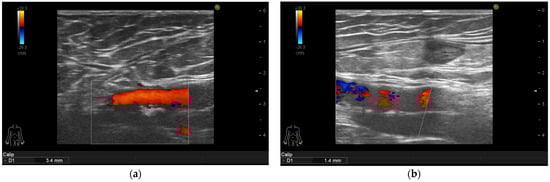

3.4. Ultrasonographic Findings

| Intima media thickness of the right femoral arteries (mm) | 0.9 (0.8–1.05) | 0.7 (0.5–0.9) | <0.001 |

| Intima media thickness of the left femoral arteries (mm) | 0.8 (0.6–1.1) | 0.7 (0.5–0.8) | <0.001 |